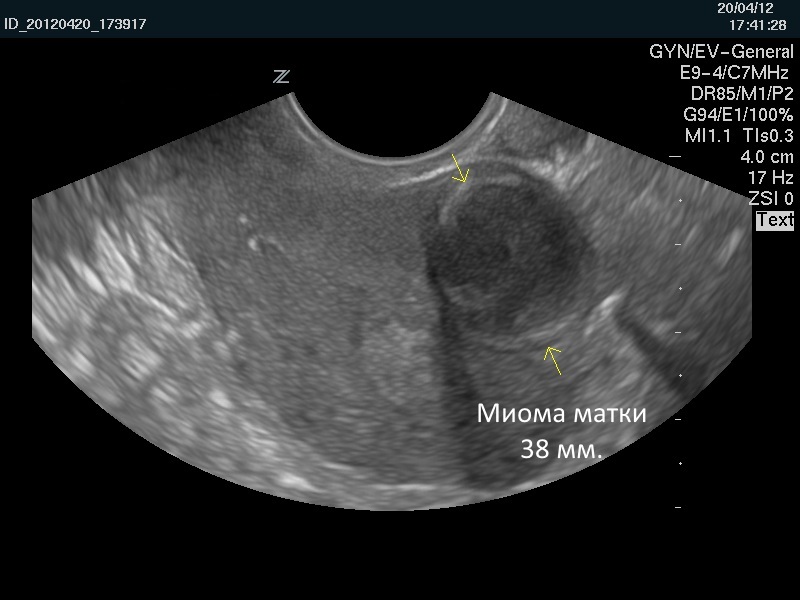

Размер миомы определяется с помощью УЗИ. Ее описывают в неделях и в сантиметрах. По мере роста новообразования матка увеличивается так же, как и во время беременности. То есть в случае увеличения матки на 10 неделе беременности женщине ставится диагноз «миома 10 недель». Размеры в неделях и см таковы:

Ультразвуковое исследование (УЗИ) является одним из наиболее распространенных и доступных методов диагностики миомы матки. С помощью УЗИ можно получить информацию о размере, количестве и расположении миом. Исследование может проводиться как трансабдоминально (через переднюю стенку живота), так и трансвагинально (через влагалище), что позволяет получить более четкие изображения. УЗИ также помогает отслеживать динамику роста миомы на протяжении времени, что особенно важно для оценки рисков.